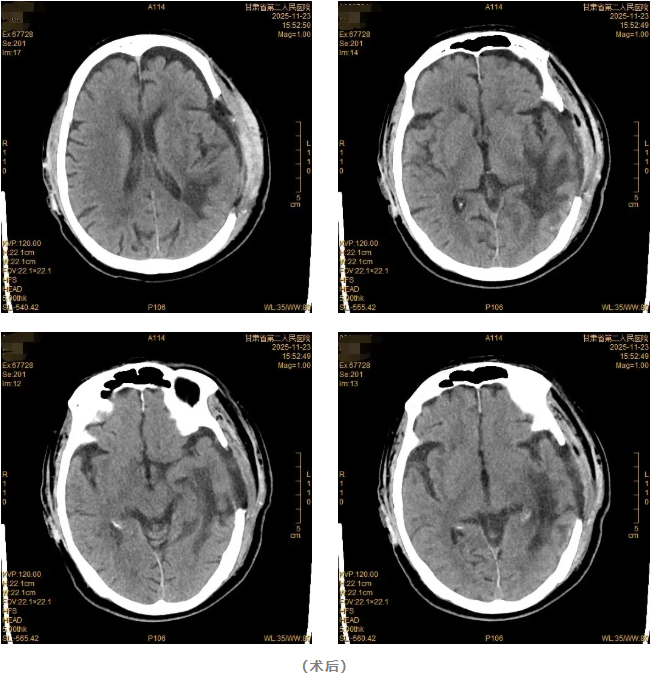

该患者因“突发意识不清伴右侧肢体无力9小时”由120急救车送至我院。急诊查头颅CT显示:左侧颞顶叶脑出血,出血量约70ml。神经疾病中心团队迅速完善术前准备后,急诊为患者施行开颅血肿清除手术。手术过程顺利,术后患者意识逐渐恢复清醒,复查头颅CT确认颅内血肿已清除。

术后早期,患者在重症监护室(ICU)接受严密监护与治疗,生命体征平稳后转入普通病房继续康复。在神经疾病中心医护团队的精心治疗与康复指导下,患者肢体力量逐步好转,能够在辅助下下地行走,恢复进展良好。